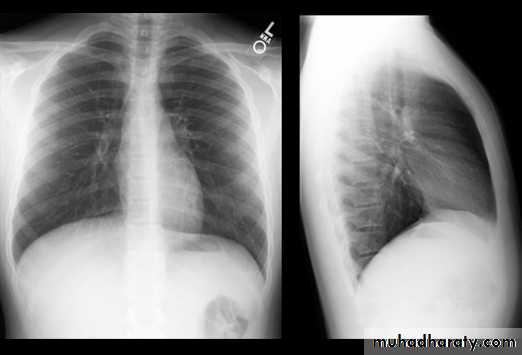

Normal chest XR PA & lateral view

1,2,3 .presentation4.normal chest film ( PA ) view

8.normal chest XR PA & lat. view

32.RT ML consolidation ( PA & lat. view )

33.RT ML consolidation (Lat. view )

34.LUL consolidation (PA & Lat. View )

35.LT.lower lobe consolidation ( PA & Lat. view )